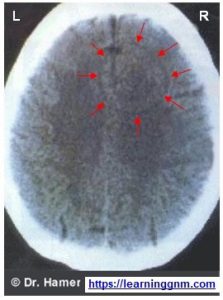

הצעד השני במחקר היה צילומי CT של המוח של כל אותם חולי סרטן שהגיעו למחלקה והסכימו לכך.הממצא המפתיע היה, שאצל כל אחד מהנבדקים הופיעה במוח צורה של נקודה עם מעגלים קונצנטריים סביבה, מה שמזכיר את העיגולים שנוצרים בבריכת מים סביב אבן שזורקים למים, או מה שמזכיר צורה של מטרת ירי.

הרדיולוגים של אז הכירו את התופעה אך היו בטוחים שזו תקלה (artifact) של המערכת. ד”ר האמר מסר את הצילומים לבדיקה של טכנאי חברת סימנס, יצרני ה-CT בו השתמש האמר והם אישרו שהעיגולים האלה אמיתיים לגמרי. המשך המחקר היה לא פחות מפתיע: העיגולים האלה (שנקראים כיום HH – ראשי תיבות בגרמנית של “הפוקוס של האמר”) הופיעו אצל כל אדם במיקום שונה במוח והמיקום היה תמיד באותו מרכז במוח ששולט על האיבר או הרקמה בגופו של החולה ששם התגלה אצלו הסרטן!

אצל כל הנבדקים שאובחנו עם סרטן במעי הגס, הופיע ה-HH בגזע המוח, במרכז ששולט על רירית המעי הגס.אצל כל הנבדקות שאובחנו עם סרטן בצינורות החלב בשד ימין הופיע ה-HH באונה השמאלית של הקורטקס הסנסורי, במרכז ששולט על רקמת תאי האפיתל הקשקשיים אשר מרפדת את הדפנות הפנימיים של צינורות החלב בשד ימין.אצל כל הנבדקות שאובחנו עם סרטן בבלוטות החלב בשד שמאל, הופיע ה-HH בצד ימין של המוחון (הצרבלום), במרכז ששולט על בלוטות החלב שבשד שמאל.וכן הלאה.

ככל שהצטברו יותר בדיקות, נעשה ברור שיש כאן חוקיות עקבית וחד-משמעית אשר מראה שיש קשר ישיר בין הטראומה/קונפליקט לבין סוג המחלה, מיקומה בגוף ומיקום ה-HH במוח. יותר מכך – הסתבר שהמודל הזה נכון לכל סוגי המחלות שנגרמות מקונפליקטים (שהם למעשה מרבית סוגי המחלות) ולא רק מחלות סרטן.כך ניתן לגלות לגבי כל סוג של מחלה איזה סוג קונפליקט או טראומה גורמים לה.התקבל למעשה מודל מדעי המאפשר לגלות מה גורם לכמעט כל סוג של מחלה וגם להוכיח זאת.בקישור שכאן ישנו פירוט (באנגלית) של מספר מחקרים ובדיקות אשר עשו חוקרים ורופאים שונים לבחינת אמינותו של מודל זה, והממצאים שלהם תאמו ב-100% את אלה של ד”ר האמר Verification.

- לפי מיקום ה-HH במוח ניתן לדעת מה היה סוג הטראומה (או “הקונפליקט הביולוגי” כפי שזה נקרא כיום ברפואה החדשה) והיכן צפויים להופיע בגוף תסמיני המחלה.

- לפי תסמיני המחלה ומיקומם בגוף ניתן לדעת מה היה הקונפליקט שגרם למחלה והיכן יופיע ה-HH בצילום CT של המוח.

- לפי סוג הקונפליקט שהאדם חווה ניתן לדעת מהי המחלה שצפויה להתפתח בגופו והיכן יופיע ה-HH בצילום CT של המוח.

ההצלבה של סוג הקונפליקט↔HH↔הסימפטומים היא כנראה המודל הרפואי היחידי הקיים כיום שבעזרתו ניתן לגלות ולהוכיח בצורה מדעית את הגורם לכל סוג של מחלה.במשך חייו הצטברו אצל ד”ר האמר מעל 50,000 מקרים מתועדים.על בסיס ממצאיו הוא פרסם טבלאות והסברים מפורטים המאפשרים לרופאים ומטפלים שלמדו את הרפואה החדשה לדעת במרבית המקרים מה היה גורם המחלה אצל המטופל הספציפי, גם בלי צורך לעשות לו צילום CT של המוח.

ההערכה של הרפואה החדשה אומרת שכ-95% מהמחלות נגרמות מקונפליקטים/טראומות שניתן לגלותן בעזרת מציאת ה-HH בצילום CT של המוח.שאר כ-5% מהמחלות נגרמות בגלל רעלים שונים וקרינות, בעיקר קרינות מייננות.

בהחלט כן. זה לא לנבא וזו לא הנדסה הפוכה אלא סימנים שניתן לראות בצילום CT של המוח. אפשר לדעת לפי זה את הדברים הבאים:

4. האם הקונפליקט עדיין פעיל, או שהוא נפתר והאדם נמצא בחצי הראשון של שלב הריפוי או בחצי השני של שלב הריפוי או שהאדם החלים לגמרי מהמחלה.

אחת הבעיות היא שהרדיולוגים מתייחסים לתופעת ה-HH כתקלה ולא כמשהו אמיתי.

בעיה נוספת היא שכדי לקבל תוצאות מספיק מדוייקות צריך לכייל את מכשירי ה-CT לרזולוציה יותר טובה ממה שמקובל כיום (למיטב ידיעתי צפיפות החתכים של צילומי ה-CT צריכה להיות בערך פי 3 גדולה מזו המקובלת כיום).